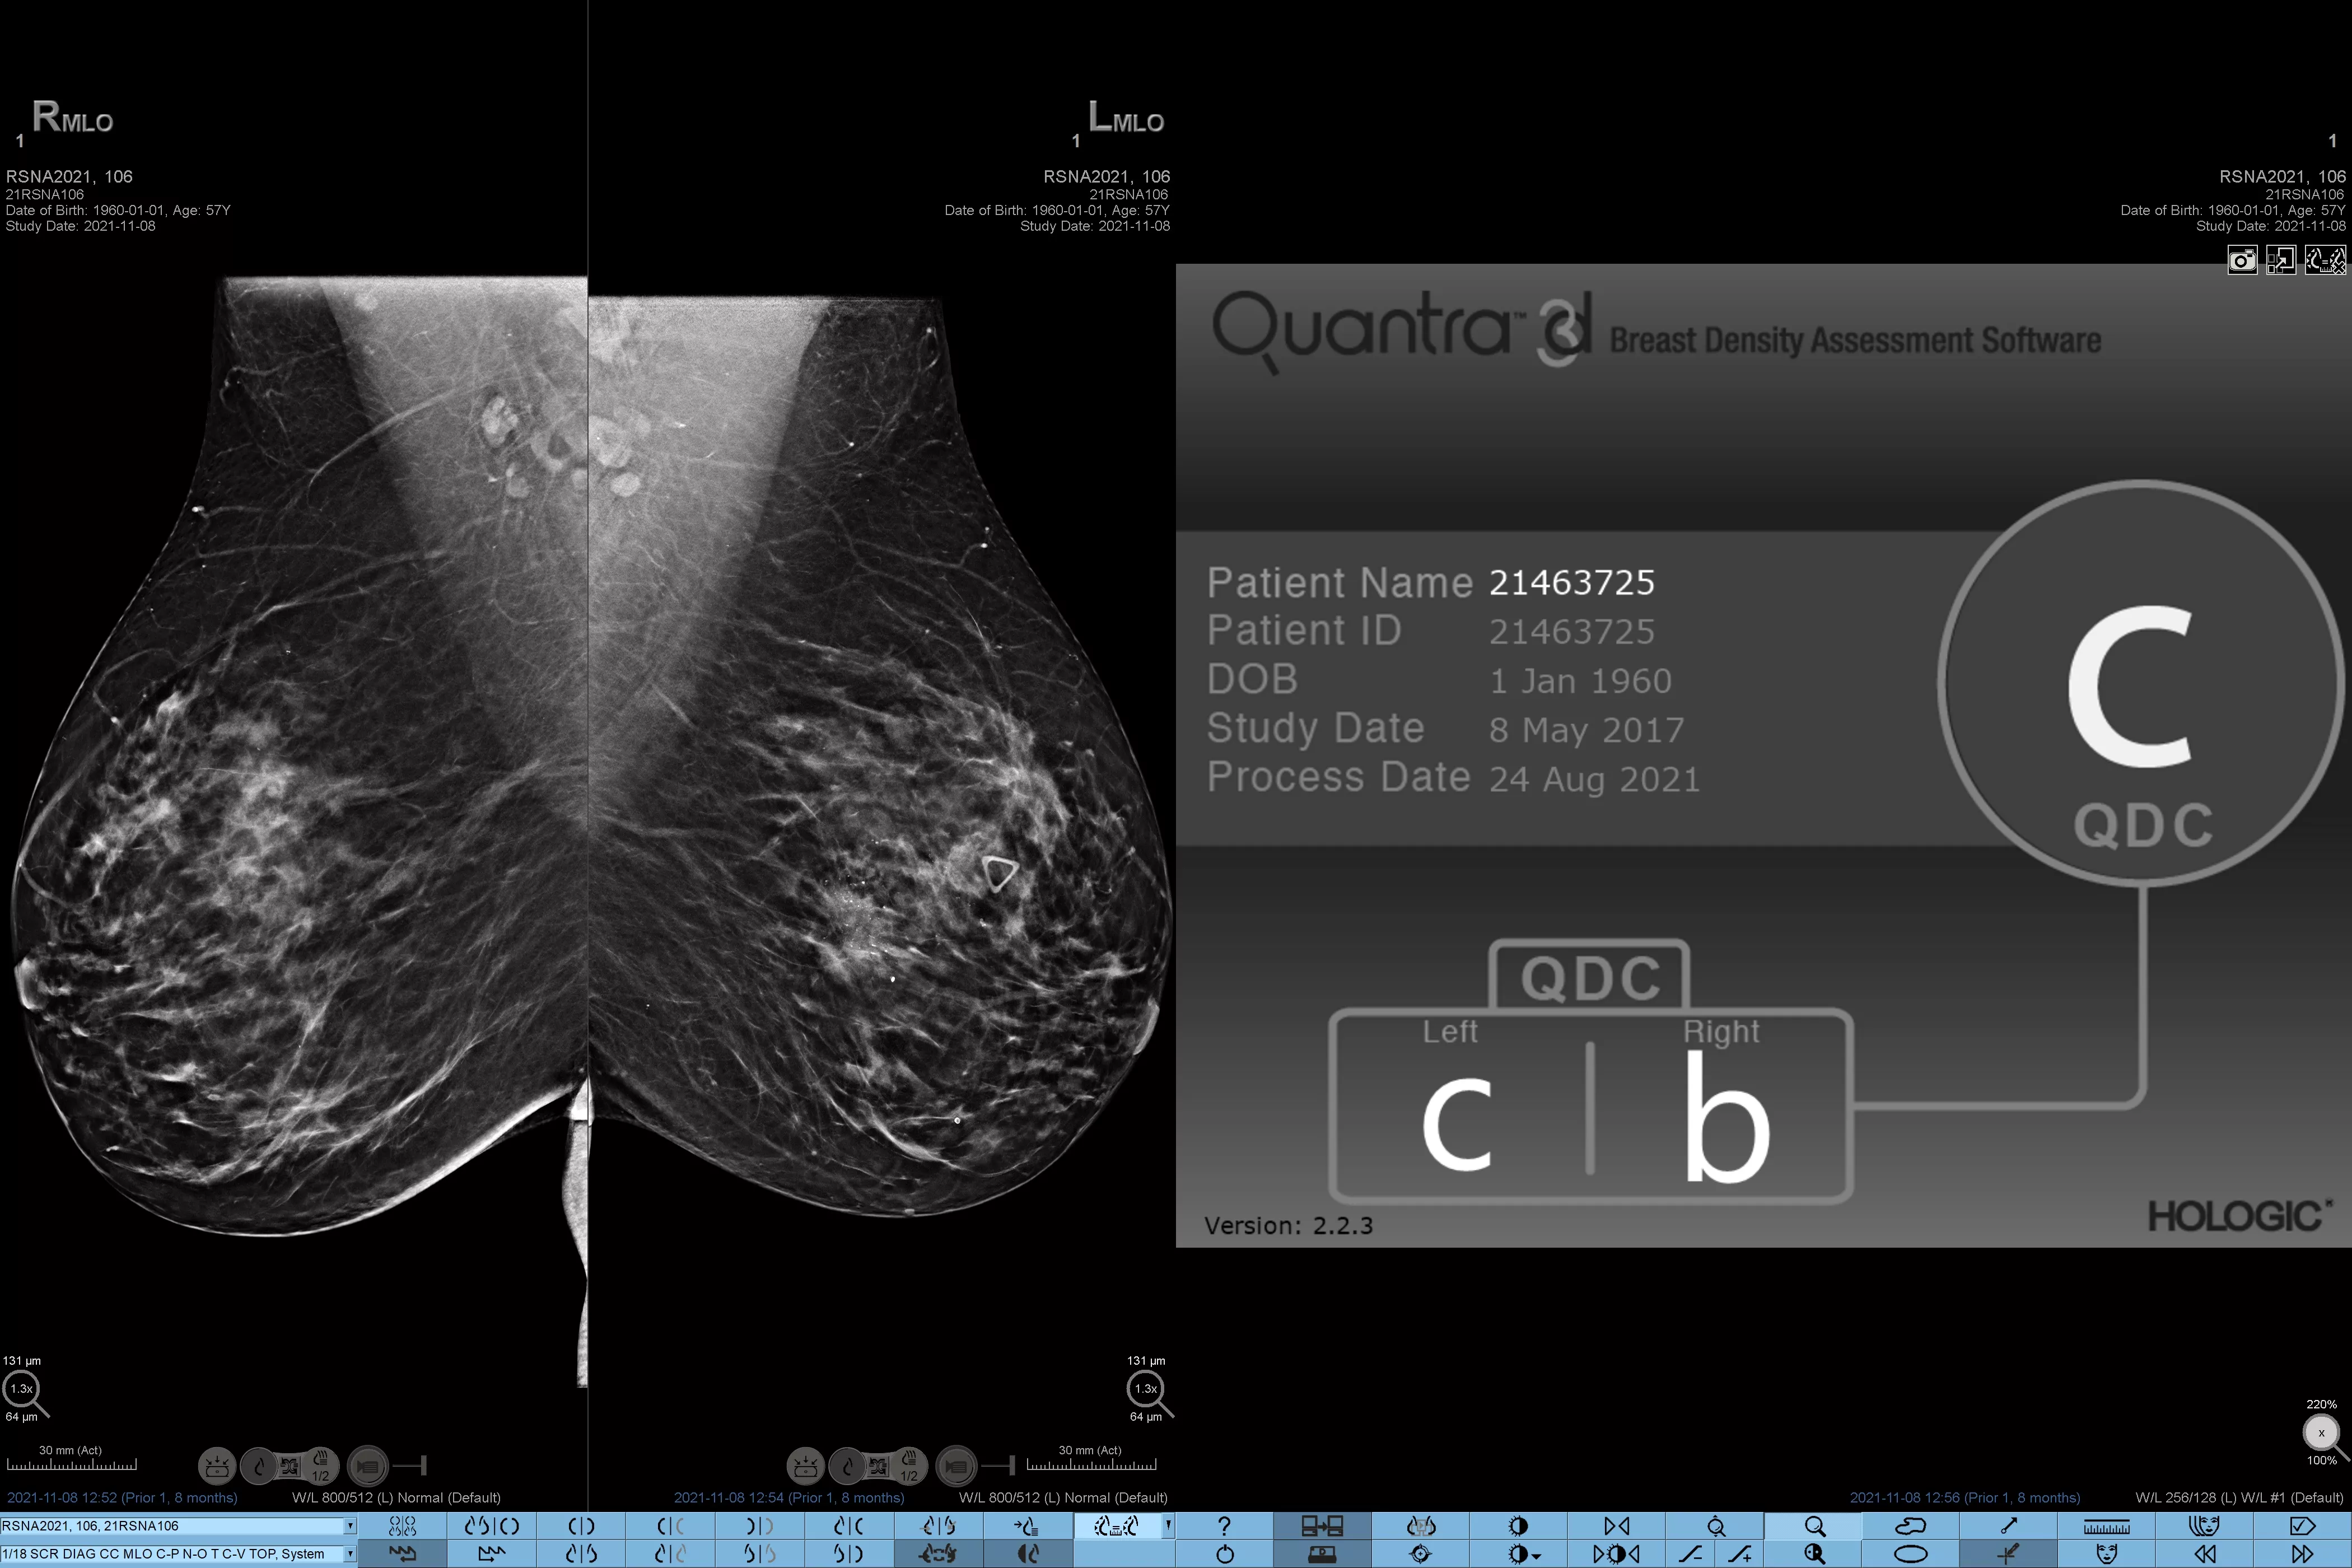

Higher breast density is known to increase a woman’s risk for breast cancer.1 The need for accurate, unbiased analysis is therefore critical. Powered by machine learning, Quantra technology software analyses both 2D™ and tomosynthesis images for distribution and texture of parenchymal tissue. It categorises breasts in four breast composition categories consistent with guidance from the American College of Radiology (ACR) BI-RADS Atlas 5th Edition.2

In addition to volume, pattern and texture of fibroglandular tissue may play just as an important role in mammographic cancer risk prediction.3-5 By analysing and categorising breast texture and pattern, our technology can deliver the accurate information you need to achieve more consistent and reliable scoring and confidently design patient-specific screening.

Objective machine learning algorithm that assigns breast density category based on analysis of breast tissue texture and patterns.

Quantra software’s unbiased algorithm analyse both 2D and tomosynthesis images to support your analysis by:

• Overcoming subjectivity in visual assessment, providing more consistent, and more reliable scoring.*

• Elevating the standard of care and standardises reporting.

*Scores are based on ACR BI-RADS categories, in line with the revised guidance by the American College of Radiation (ACR) BI-RADS Atlas 5th Edition. This accounts for pattern and texture, compared with volume, when determining density.